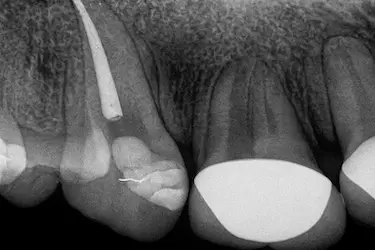

Se realizan pruebas de sensibilidad y una radiografía periapical o panorámica para confirmar si existe daño pulpar o inflamación en la raíz.

Estas imágenes ayudan a planificar el tratamiento de conducto con precisión.

Antes de finalizar, el odontólogo realiza una radiografía de control para confirmar que el sellado está correcto y que no hay signos de infección.